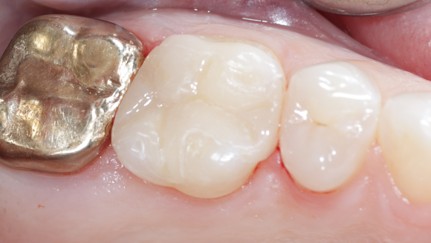

Extensive training and experience give prosthodontists a unique understanding of restoring the dynamics of a smile and healthy mouth with the creation of tooth prostheses. Becoming a prosthodontist requires an additional three years of specialty training after obtaining a DMD (Doctor of Dental Medicine) or DDS (Doctor of Dental Surgery) degree.